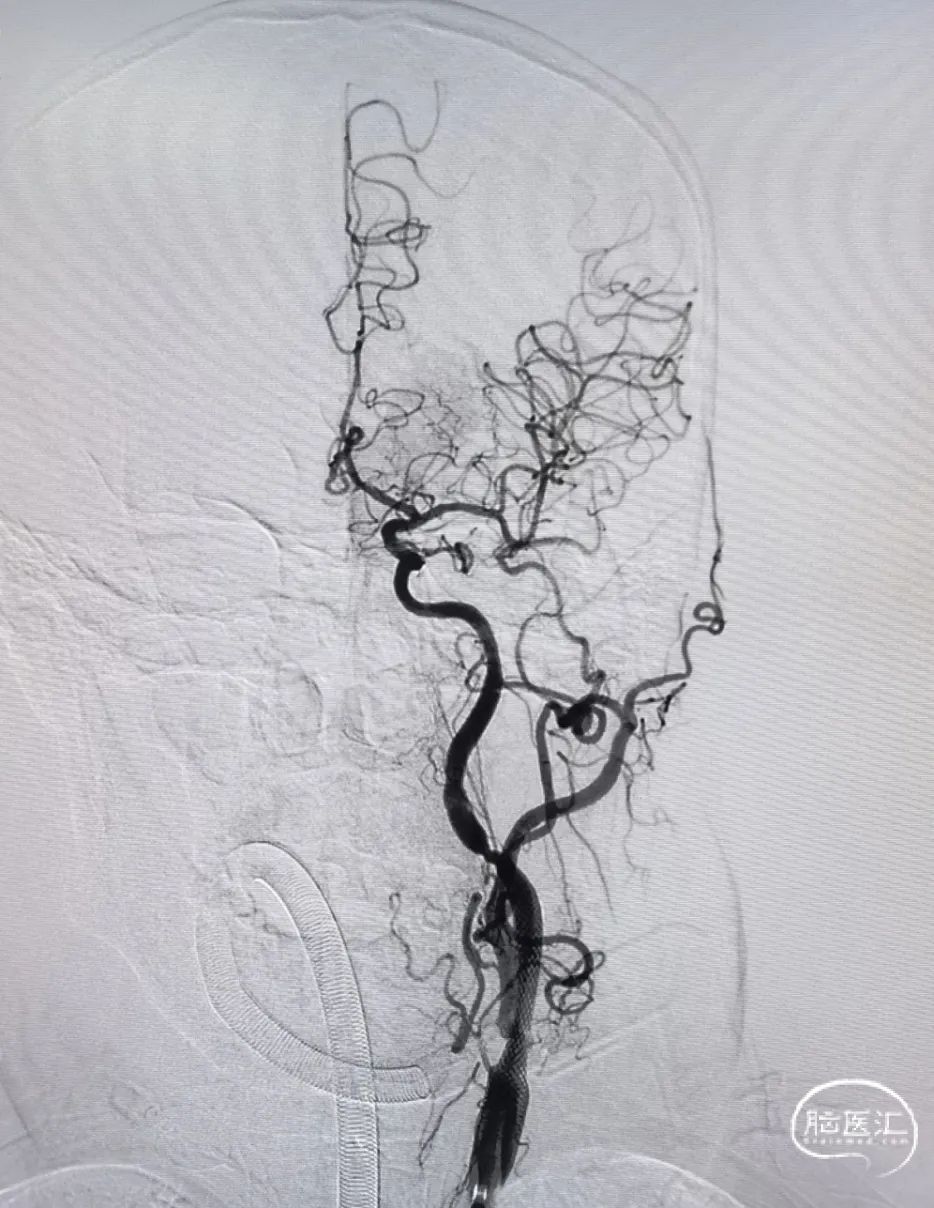

术后正侧位造影:全程血流恢复满意。

大脑中动脉取栓一把通。

再次超选并将Syphonet®取栓支架释放后造影见血流通畅,回收取栓支架后血管再次闭塞,遂将4.5*28mm 支架置于大脑前动脉释放,支架释放后造影血流恢复满意。

通过中间导管将保护伞到位,退出中间导管,长鞘退至颈总动脉,4.5*30mm 球囊扩张颈内动脉狭窄段,球扩后满意,释放7*40mm 支架。